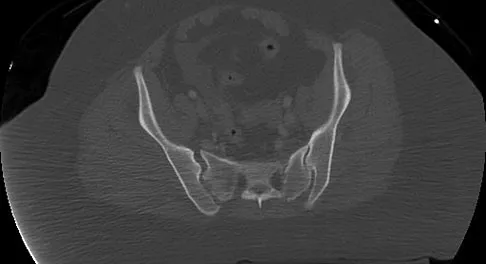

Question 18

A 13-year-old girl has had increasing left hip pain for the past 4 months. A radiograph, bone scan, MRI scan, and photomicrograph are shown in Figures 1a through 1d. Which of the following immunohistochemistry results would confirm the most likely diagnosis?

Explanation